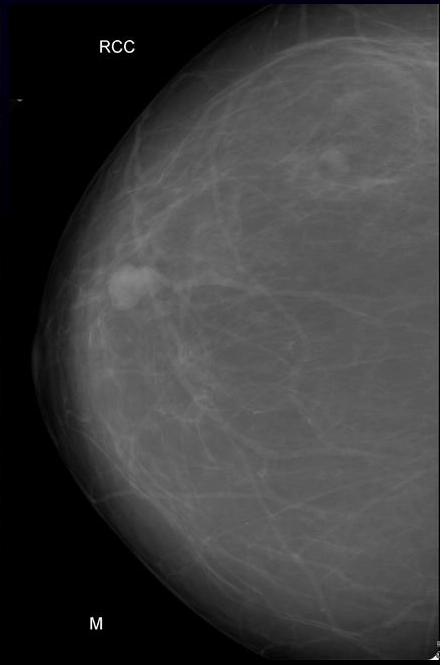

Phân loại Bi-RADS

Phân loại BI-RADS (Breast Imaging Reporting and Data System- BI-RADS)